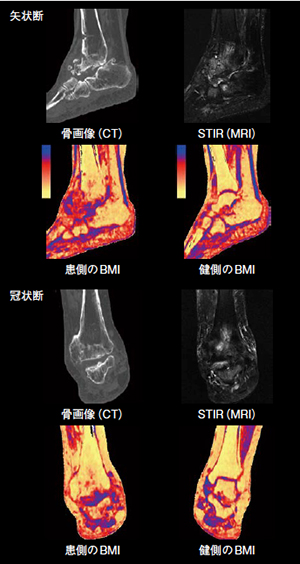

変型性足関節症における骨髄浮腫の描出

【背 景】78歳,女性。過去に右距骨骨壊死を認め手術歴あり。術後約20年の経過で右足関節の疼痛,腫脹が悪化し,足関節固定術の適応と判断され当院に紹介された。骨評価用画像に加え骨髄浮腫の状態を確認するため,Dual Energy CT(DECT)による撮影が依頼された。

【所 見】CT骨画像では距踵舟関節を主体に骨棘形成および骨癒合あり。高度な距骨下主体の変形性関節症も認められる。MRI(STIR像)では骨髄浮腫も強く,距骨や舟状骨,踵骨,立方骨の信号変化も目立つ。DECTのアプリケーションであるLiver VNC Boneを用いて解析したBone Marrow Image(BMI)では,MRI(STIR像)と比較し,矢状断で見られる距骨全体の骨髄浮腫が見られる。冠状断では,MRIの信号変化と類似した脛骨の信号変化も認められた。

【訴求ポイント】過去の解析結果から作成した当院オリジナルのカラーLUTを使用し,Dual Energyを用いたBMIに重ね合わせることで視覚的にも骨髄浮腫の評価が明確となった。また,80kV/Sn140kVの組み合わせを使用することで,100kV/Sn140kVよりも解析精度の向上と20%程度の被ばく低減が可能であった。さらに,術前に施行される両側足関節のCT検査に付随する形でDECTによる骨髄浮腫の評価を行ったことにより,健側がその範囲や程度を比較する指標として役立った。